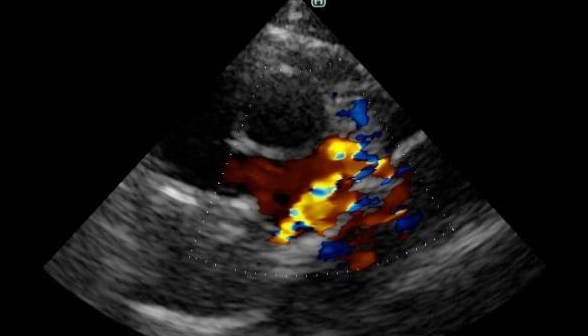

血液の流れる向きや速さを確認する検査にて、肺動脈内に乱流(黄色、緑、オレンジがモザイク状に混ざっている部分)が確認されました。